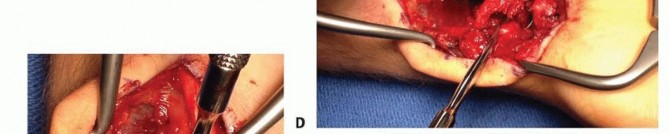

EXPOSURE

TECH FIG 4 • A. The palmar distal radius graft is harvested through the distal portion of the Henry approach to the distal forearm. B. The palmar carpal artery is exposed distal to superficial aponeurosis of the pronator quadratus.(continued)

GRAFT HARVEST

Periosteum on either side of the palmar carpal artery is incised, and the artery is gently mobilized laterallyto the radial artery.Bone graft harvest from the ulnar half of the distal radius is initiated by periosteal incision with a scalpel, followed by osteotomy and elevation with small osteotomes.Incision through the radioscaphocapitate ligament exposes the scaphoid nonunion site and allow for removal of fibrous tissue (TECH FIG 4C).